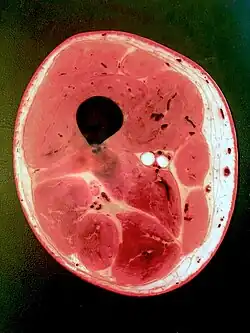

Microsopic image of a fascial structure (nuchal ligament)